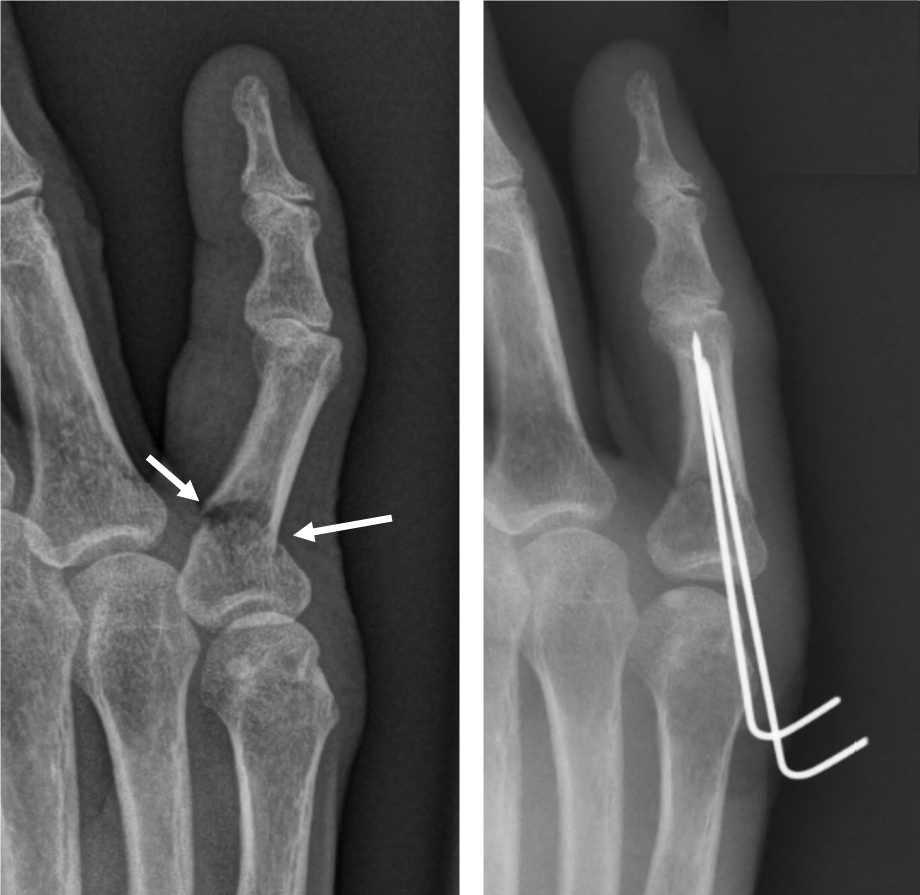

- 핀 고정 수술

- 뼈가 복합적으로 부러지거나, 어긋나서 그대로 붙으면 기능에 치명적 문제가 예상되는 경우에는 핀이나 금속판을 삽입하는 수술을 진행합니다.

- 수술 후에는 손가락 움직임을 최소화하고, 적절한 시점에 재활 운동을 시작해야 합니다.